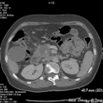

Measurements

在横断位.冠状位.矢状位上分别测量Pancreatic Ca的最大径线及Pancreatic Ca的体积测量

Axial Dmax= 40.7 mm

Coronal Dmax= 37.2 mm

Sagittal Dmax= 35.8 mm

体积:23.694 cm³